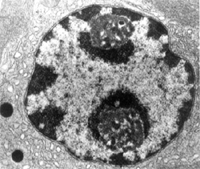

雙炔失碳酯細胞形態學變化:12μmol/LαANO作用於LNCaP細胞48h,細胞數量減少,部分細胞發生變形,細胞變圓,體積變小;24μmol/LαANO作用下LNCaP細胞形態發生明顯變化,細胞形狀變圓,體積變小,部分細胞碎裂,細胞質空泡化,細胞表面變粗糙,呈現顆粒狀,胞間粘連減少,細胞大部分為分散的個體。